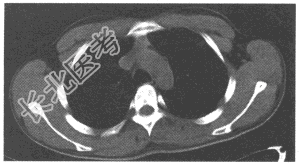

- 单项选择题女,43岁, 两眼不能完全睁开,全身无力两年余。胸部CT扫描前纵隔内发现肿块, 如图,最可能的诊断是

E、胸腺瘤